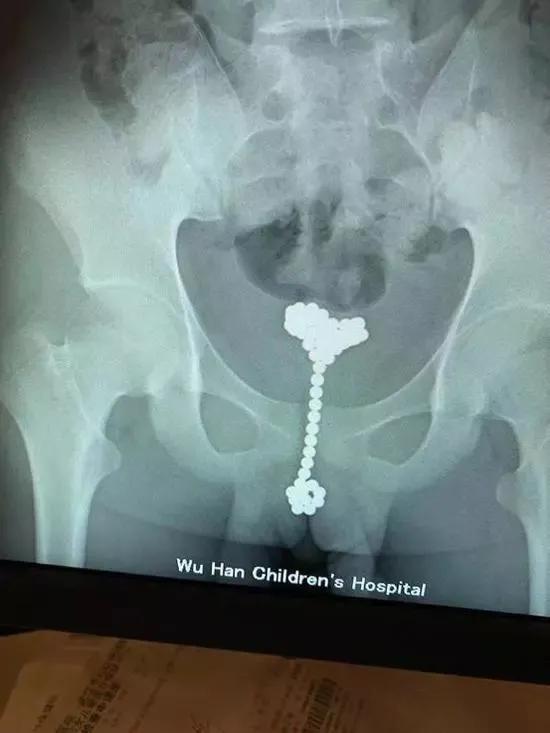

这位哥,竟然将带磁力球塞入尿道

据说还一下塞了53颗?????

究其原因竟然是对洞孔感到好奇